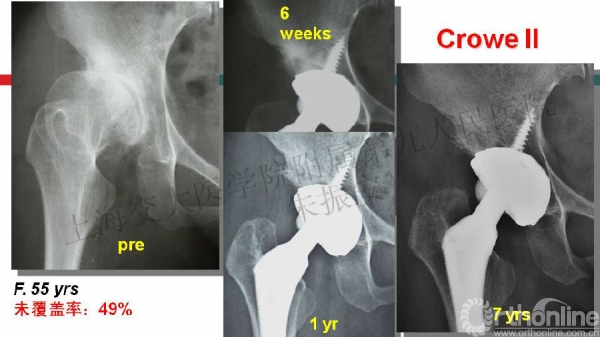

2014-07-09 文章来源:上海交大医学院附属第九人民医院 朱振安 作者:朱振安 我要说